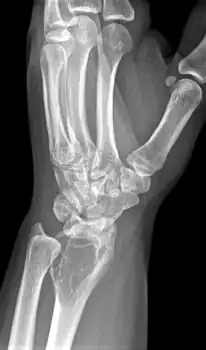

On X-ray, giant-cell tumors (GCTs) are lytic/lucent lesions that have an epiphyseal location and grow to the articular surface of the involved bone.[11] Radiologically the tumors may show characteristic 'soap bubble' appearance.[12] They are distinguishable from other bony tumors in that GCTs usually have a nonsclerotic and sharply defined border. About 5% of giant-cell tumors metastasize, usually to a lung, which may be benign metastasis,[13] when the diagnosis of giant-cell tumor is suspected, a chest X-ray or computed tomography may be needed. MRI can be used to assess intramedullary and soft tissue extension.

Front view X-ray. A well-defined expansile lesion in radius near wrist

Side view of same wrist

Front view X-ray one-year later it has grown